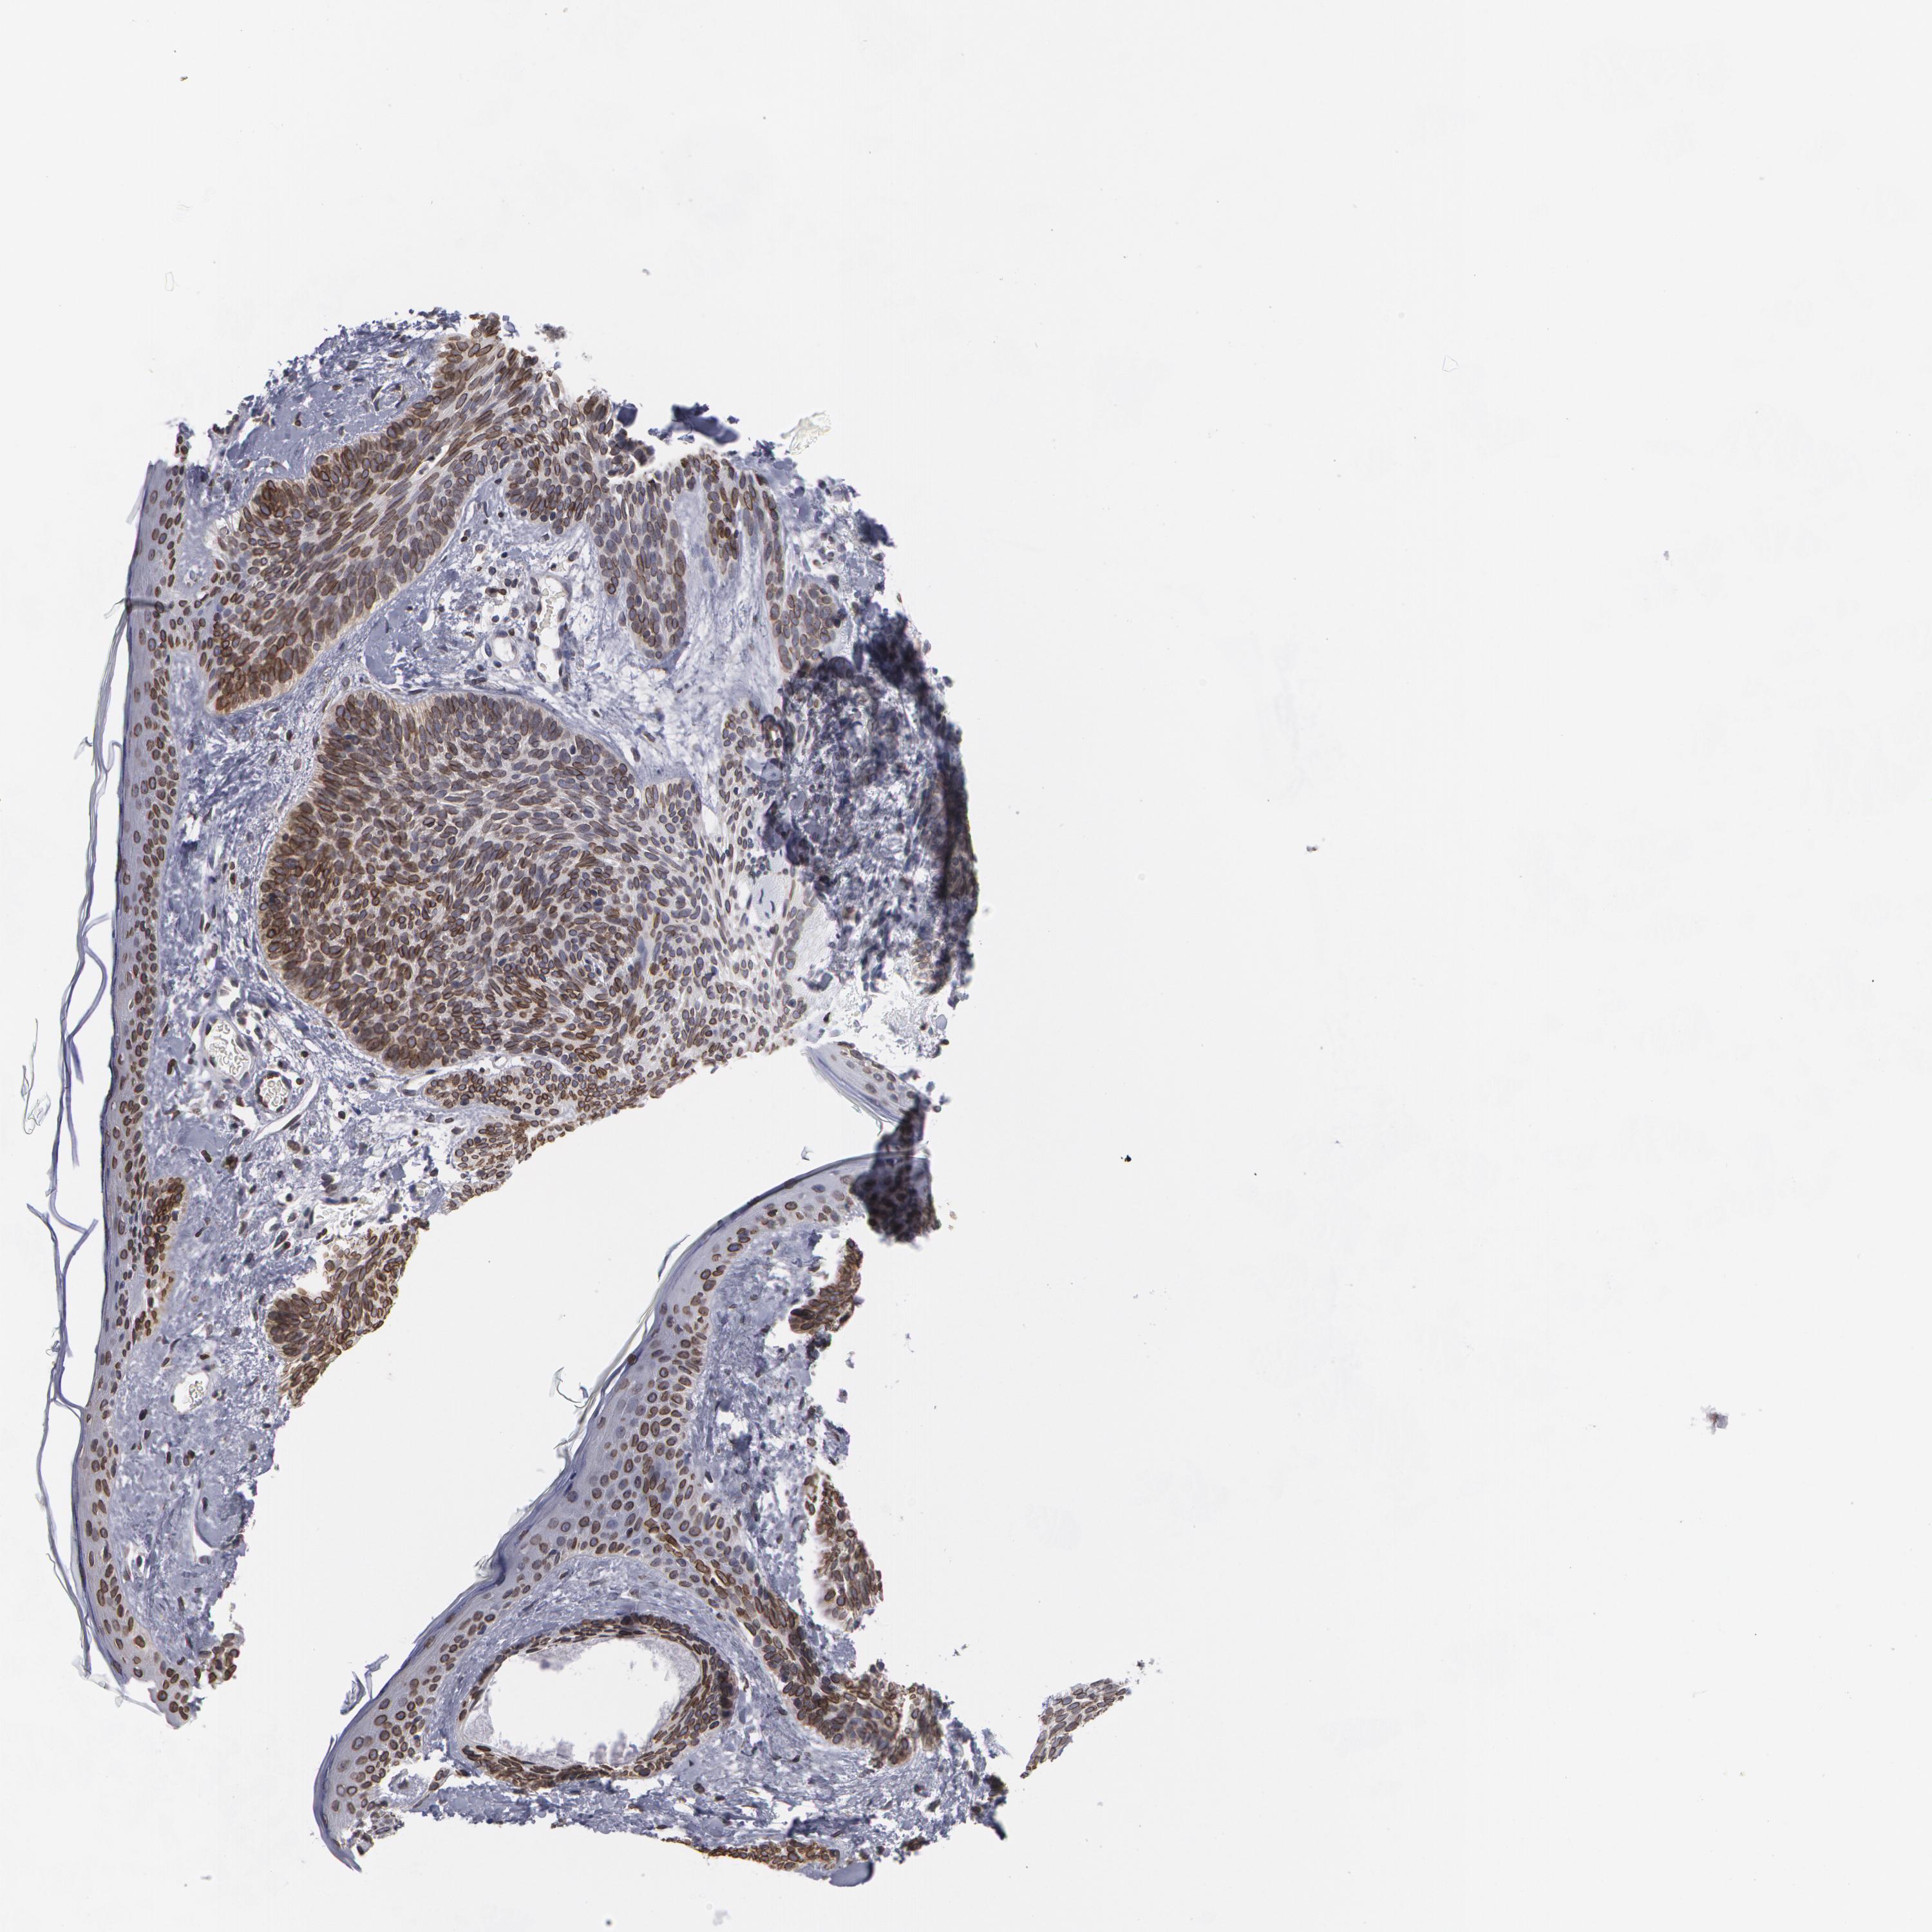

SKIN CANCER - Protein expressioni

A mouse-over function shows sample information and annotation data. Click on an image to view it in a full screen mode. Samples can be filtered based on level of antibody staining by selecting one or several of the following categories: high, medium, low and not detected. The assay and annotation is described here.

Antibody stainingi

Antibody staining in the annotated cell types in the current human tissue is reported as not detected, low, medium, or high, based on conventional immunohistochemistry profiling in selected tissues. This score is based on the combination of the staining intensity and fraction of stained cells.

Each image is clickable and will lead to virtual microscopy that enables deeper exploration of all samples and also displays staining intensity scores, fraction scores and subcellular localization as well as patient and tissue information for each sample.

Antibody HPA000609

Antibody CAB001545

Antibody CAB002029

Antibody CAB062552

Staining

High

Medium

Low

Not detected

Intensity

Strong

Moderate

Weak

Negative

Quantity

>75%

75%-25%

<25%

None

Location

Nuclear

Cytoplasmic/membranous

Cytoplasmic/membranous,nuclear

Basal cell carcinoma

Squamous cell carcinoma, NOS